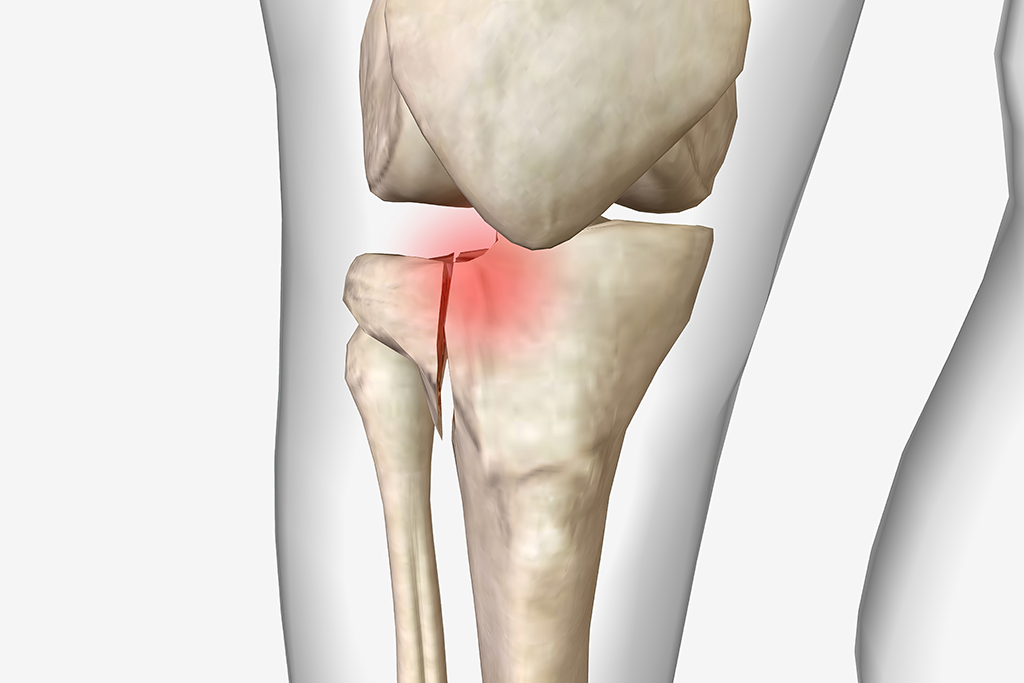

Fractura de platou tibial afecteaza partea superioara a tibiei, implicata direct in functionarea genunchiului. Este o leziune care poate compromite stabilitatea, mobilitatea si calitatea vietii pacientului.

Platoul tibial are doua componente esentiale:

platoul medial (intern) – mai mare si usor concav;

platoul lateral (extern) – mai mic si usor convex.

Aceste structuri distribuie greutatea si absorb socurile. O leziune la acest nivel afecteaza intregul membru inferior.